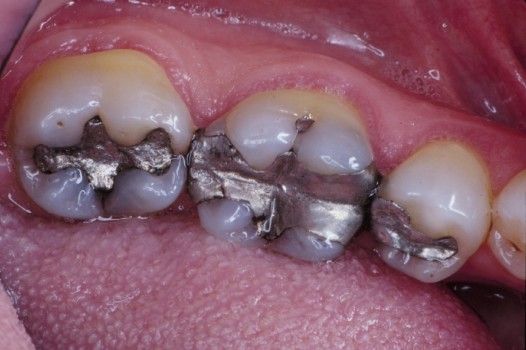

Traditional amalgam (mercury) fillings have been used for over a century, but concerns about health risks, tooth fractures, and long-term decay have led many dentists to adopt modern alternatives. Today, metal-free restorations offer healthier, stronger, and more natural-looking results.

Using advanced resins, ceramics, and state-of-the-art bonding techniques, Dr. Klim can restore teeth with precision, preserving healthy tooth structure while preventing fractures, bacterial invasion, and future toothaches.